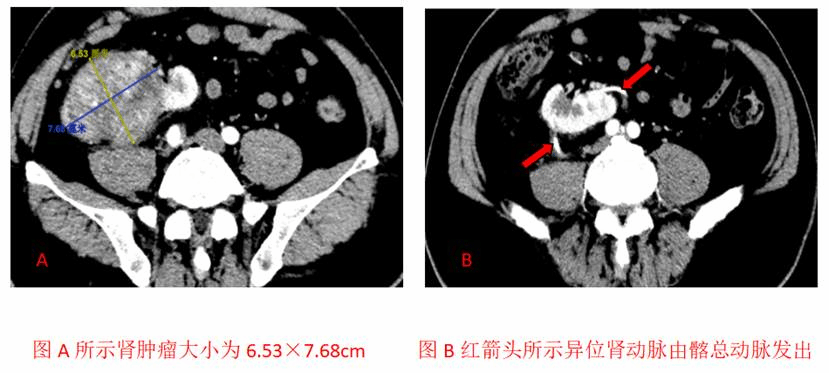

在充分的术前准备后,王春阳教授及其团队行机器人辅助下腹腔镜右肾根治性切除术,术中发现肾脏呈横位,且肾脏与结肠等周围组织粘连,最特殊的是患者的肾动脉不是由常规的腹主动脉发出,而是由左侧髂总动脉腹背侧,各发出一条肾动脉。分别夹闭肾动脉及肾静脉和输尿管,完整的切除右侧异位肾及肾癌。手术进展顺利,出血量极少。术后患者恢复较快,术后引流量较少,在术后第二天就拔除尿管及引流管,患者下地活动,未出现任何不适,第三天患者状态良好,出院。